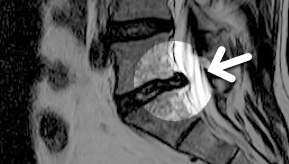

MRI ġ

MRI